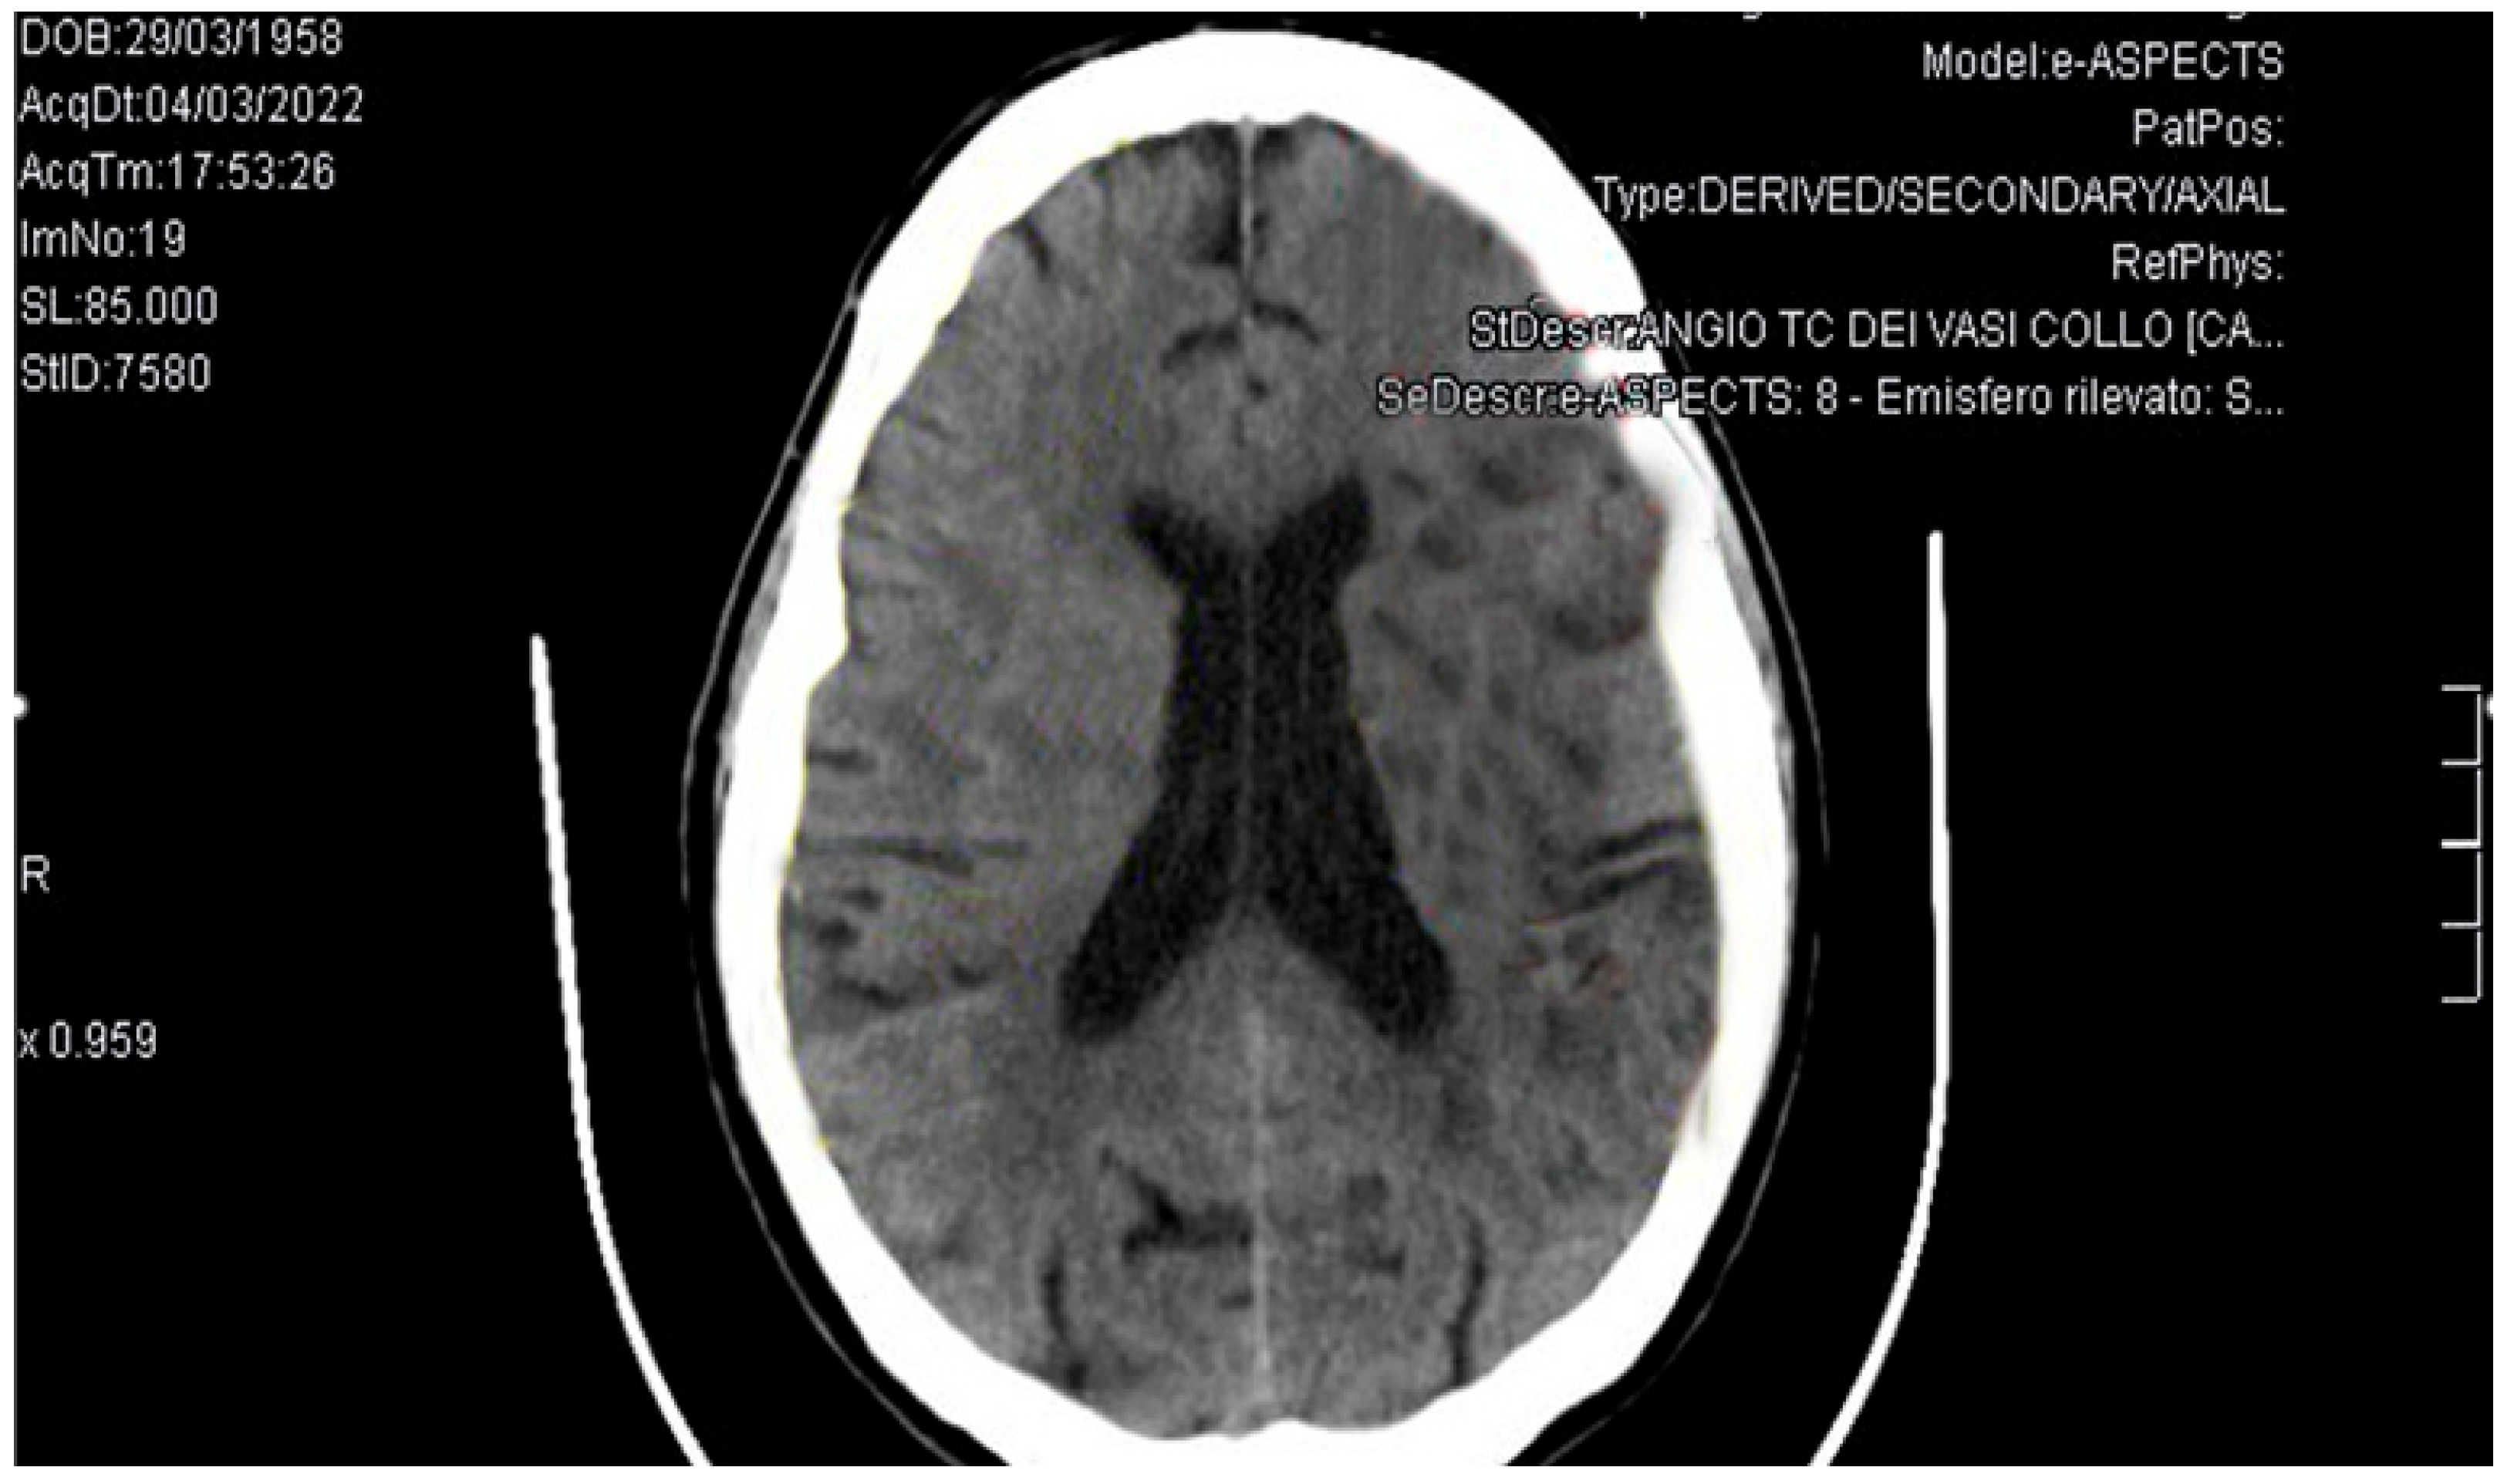

2. Case Presentation